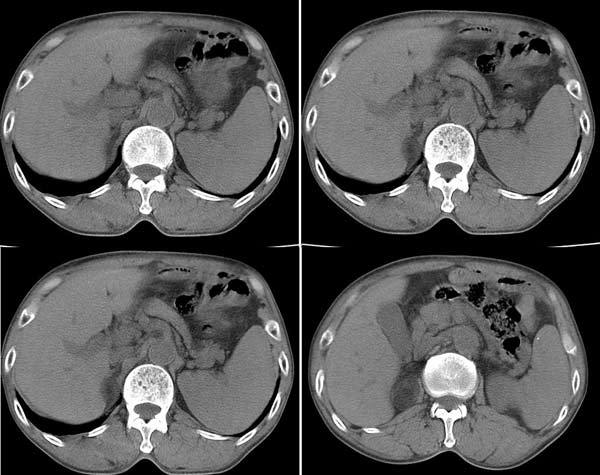

病人手下肢水肿,血压正常,无其他异常表现.

b超发现右肾上腺区占位,ct平扫见由肾上腺低密度占位性病变,病灶边界清楚,密度不均,ct值-20--60hu.

不做增强很难诊断。平扫看右肾上腺内支低密度占位与肾上级分不清,病变大体呈椭圆形,内有囊性部分,也有实性部分。考虑为嗜络细胞瘤

从值上看,考虑肾上腺骨髓脂肪瘤.不除外肾上极错构瘤.扫描层面好象不连续并且扫描厚.

右肾上腺低密度结节,无明显脂肪成分,临床无高血压,可除外肾上腺骨髓脂肪瘤及嗜络细胞瘤,考虑肾上腺腺瘤

右肾上腺低密度结节,ct -20----60hu .临床无高血压,可除外嗜络细胞瘤,考虑肾上腺髓样脂肪瘤或无功能性腺瘤[水肿提示病变引起肾上腺功能低下]

有明显的脂肪成分,考虑骨髓脂肪瘤。

右肾上腺低密度结节影,显然密度较低和脂肪差不多未见高密度分隔考虑肾上腺原醛腺瘤,建议临床检查相关的生化指标。脾大,并见高密度钙化点。

肾上腺内含有脂肪成份,可以定性为骨髓脂肪瘤。

肾上腺肿瘤可以肯定,没有强化,很难定性,但从平扫特点多考虑无功能性肾上腺腺瘤.